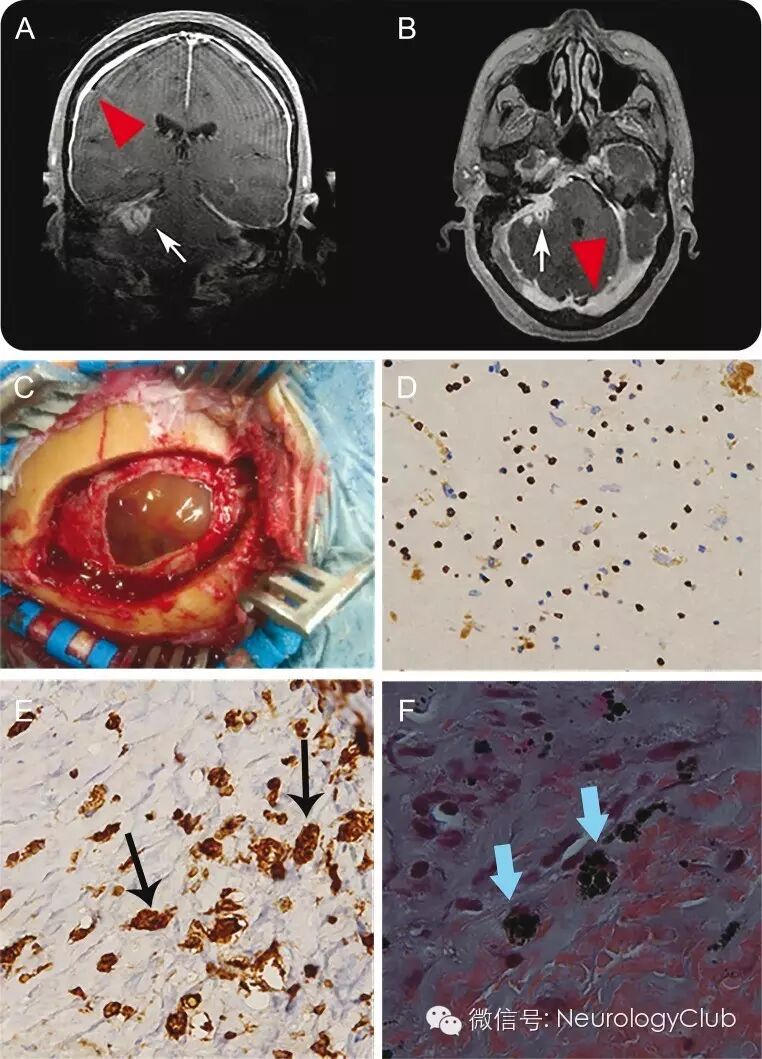

(A-B:可见弥漫结节状硬脑膜增厚强化,右侧桥小脑角区非均匀强化软组织肿块,累及内听道;C:硬脑膜弥漫褐色变;D:可见CD3+ T细胞;E:可见富含黑色素颗粒的CD68+巨噬细胞;F:Fontana-Masson染色证实巨噬细胞内存在黑色素颗粒)